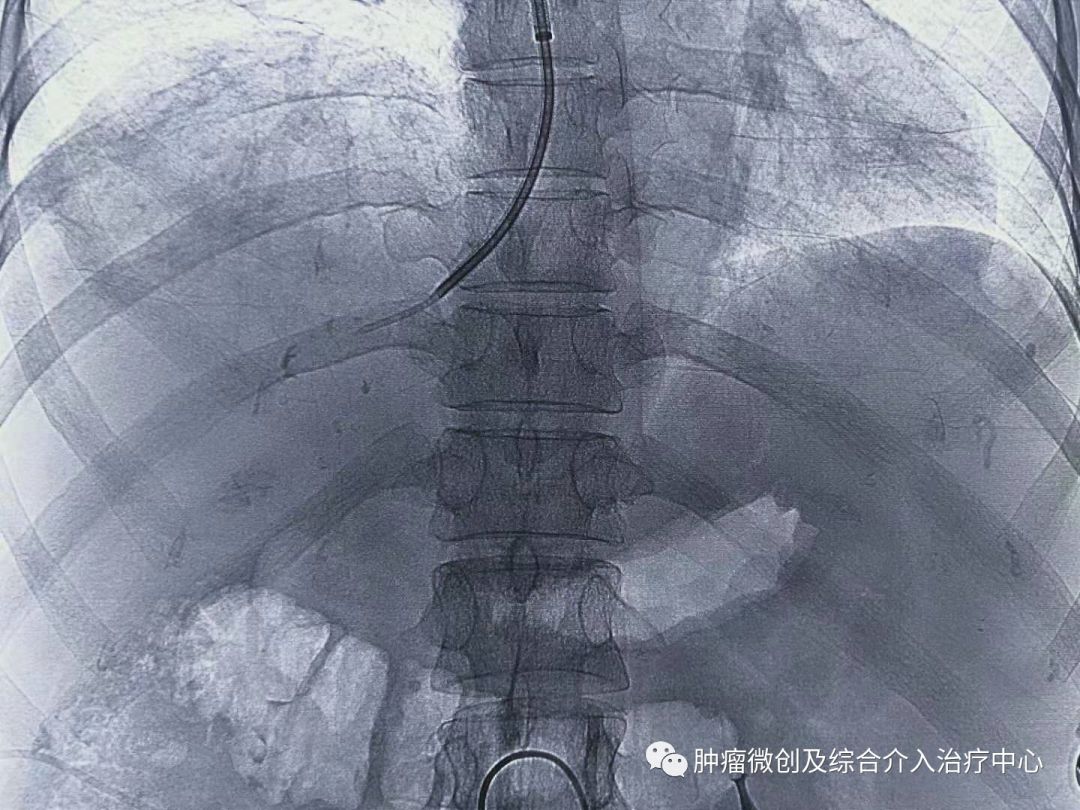

术前定位穿刺部位:

经过静脉穿刺进入门脉系统: